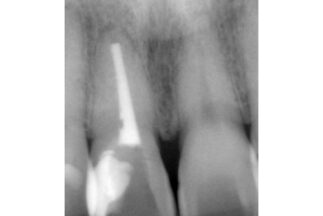

| 治療内容 | 右側上顎中切歯を抜歯しインプラント埋入をおこなった。上部構造装着後12年経過。 |

| リスクについて | 歯肉の退縮等、審美面でのリスク。 |